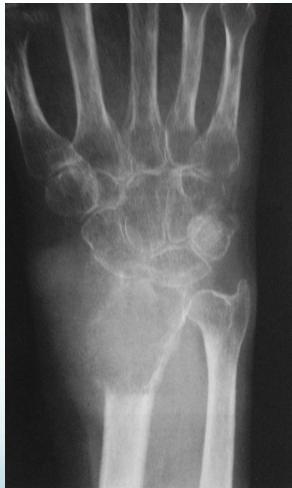

Giant-Cell Tumor

- Common sites:

- Distal radius

Radiological Features

- Eccentric lesion:

- Radiolucent

- Soap bubble

- Abuts (adjacent) against the joint

- Thin cortex

- Margins may be clear / unclear:

- Depends on aggressiveness

- Treatment:

- Curettage & bone grafting

- More wide excision in recurrent and aggressive lesions